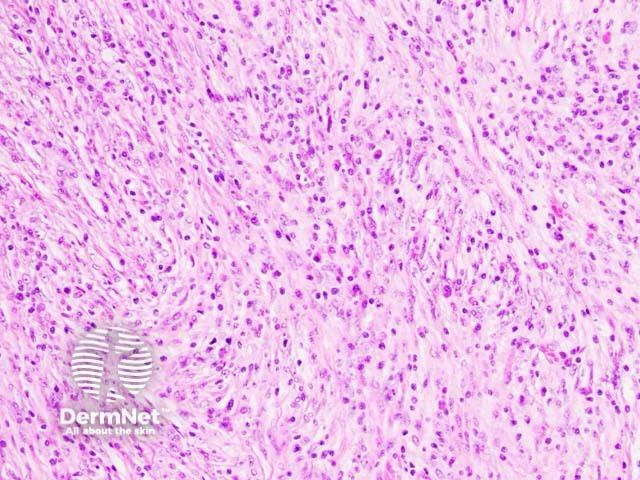

Histologically, the lesion is based in the dermis and seen underlying a normal epidermis (figure 1). The tumour is composed of an admixture of spindle-shaped and ovoid cells with a prominent inflammatory infiltrate (figures 2–3). The infiltrate is characteristically rich in plasma cells (best seen in figure 2). There may be some pleomorphism of the tumour cells and some mitotic figures (figure 3, arrow).

Figure 2